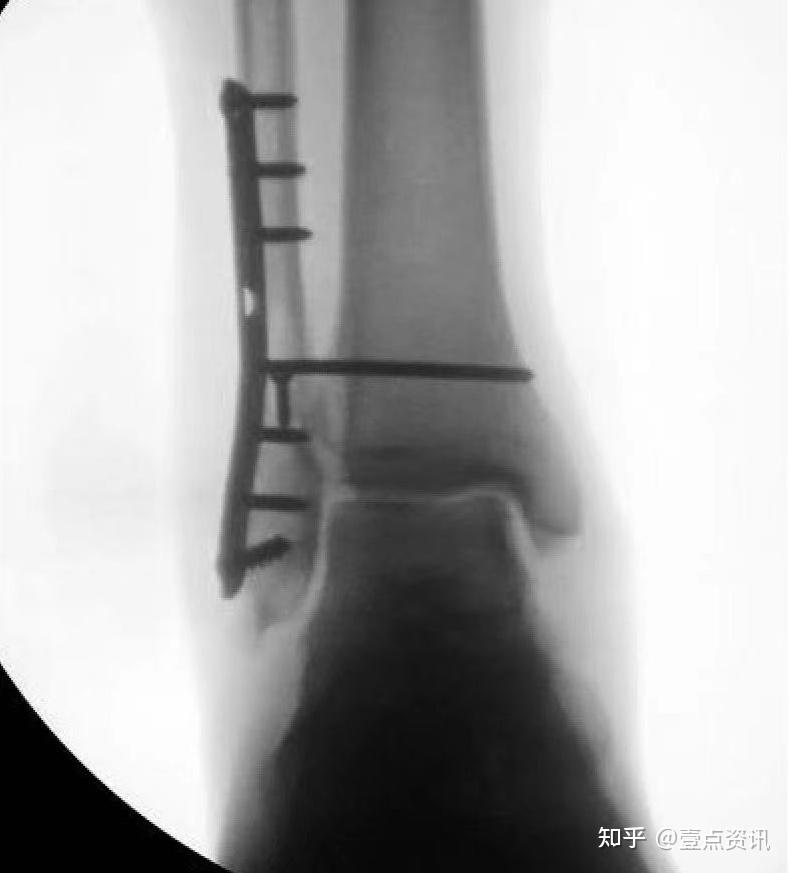

五四一总医院骨科关节病区顺利开展"锁扣带袢钛板固定下胫腓分离手术"